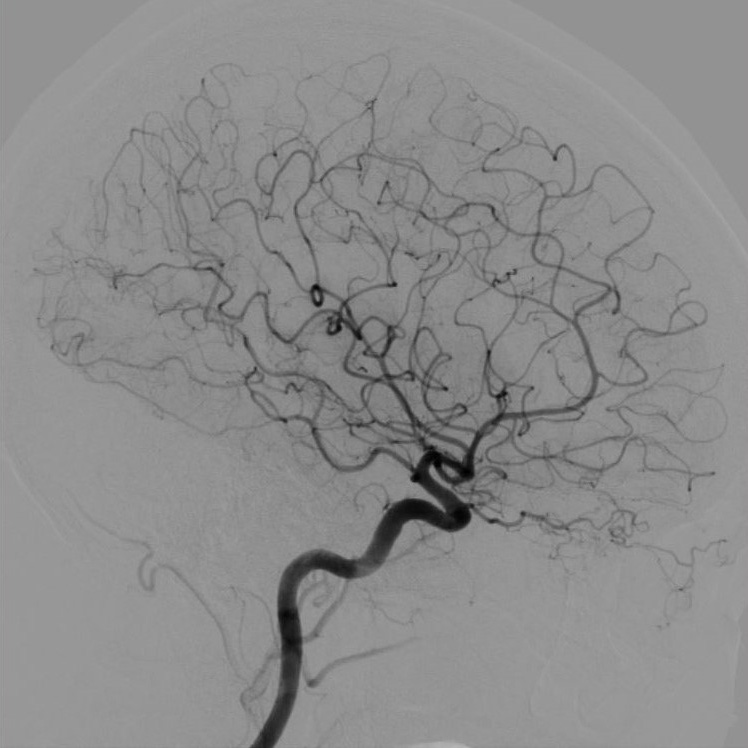

血管造影室:Alphenix (Canon)

血管造影装置は、X線TV室で使用している装置同様、X線を使ってリアルタイムで体内の情報を確認しながら手術を行う際などに使用する装置です。X線TV室と異なるのは血管造影に使用する点で、装置を動かすことによって患者さんの体の向きを変えずに、さまざまな方向から見れるような作りになっています。

血管造影とは、カテーテルと言われる細い管のようなものを、手首または足の付け根の動脈から血管内に挿入して、目的部位まで進め、造影剤を注入することで血管が描出されます。

放射線技師は主に装置の管理や画像の管理、被ばく線量の管理をしています。

・脳腫瘍の術前や脳動脈瘤、脳動脈奇形(AVM)の確認などの脳血管の造影検査(DSA)